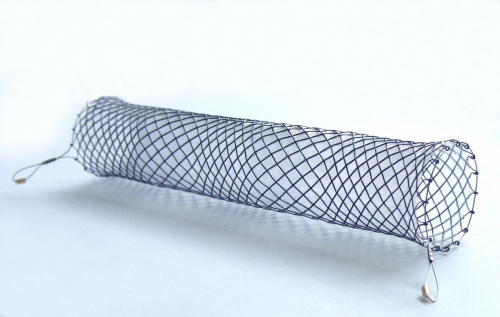

CMR VERSIUS - LEIKKAUSROBOTTIEndoskopia instrumentitEndoskopia- ja instrumentaatiopesuEndoskopialaitteetFiksaatiotuotteetGastrokirurgiaGynekologiaHemostaatitIholiimatkirurginen liimaKNKLaparoskooppinen kirurgiaMuut tuotteetNEUROKIRURGIAObstetriikka / obstetriaOrtopediaStapleritStentitSurgitel luupit, luuppivalot ja kameratUrologia